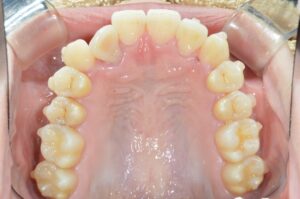

①写真撮影

今の歯並びを色々な角度から撮影します。

せっかくなので矯正前→現在(No.40)で並べてみます。